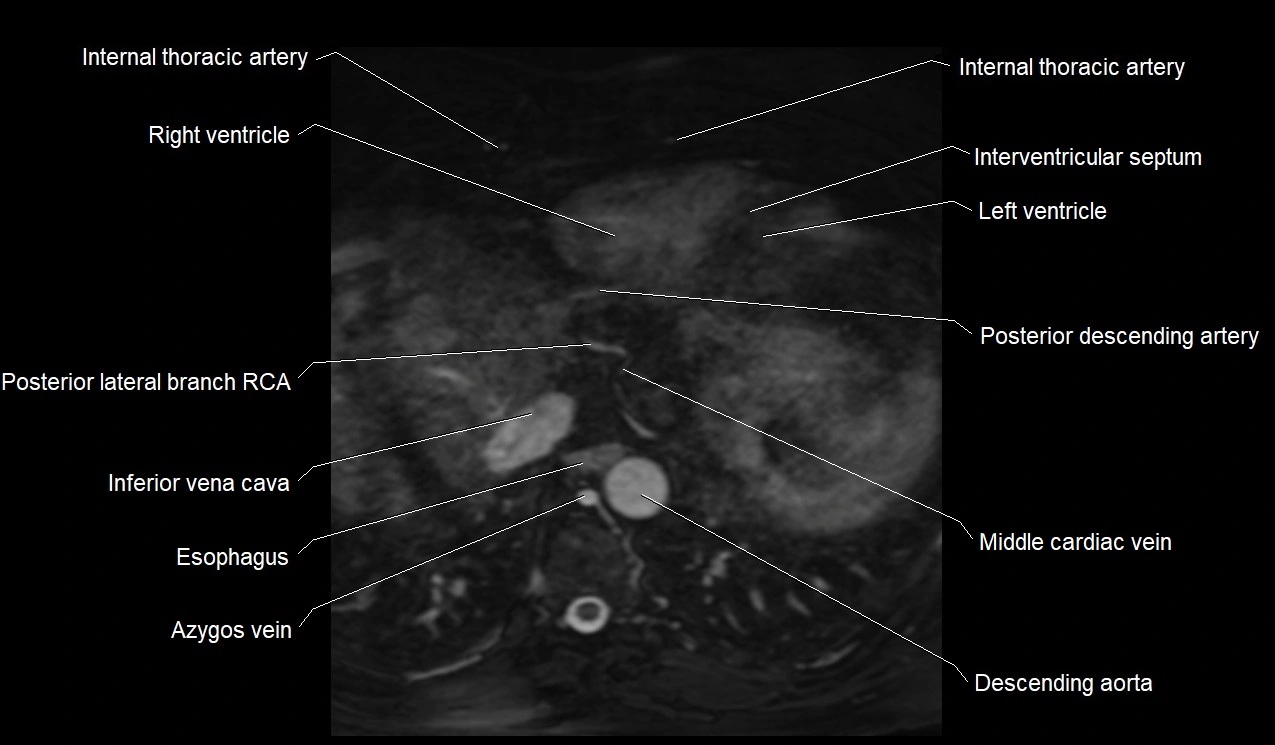

- Right ventricle

- Left ventricle

- Interventricular Septum

- Middle cardiac vein

- Inferior vena cava

- Right posterior descending coronary artery (Right PDA)

- Azygos vein

- Descending thoracic aorta